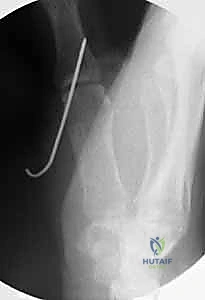

- الأشعة السينية (X-rays): ضرورية لاستبعاد وجود كسور مصاحبة (مثل الكسر القلعي Avulsion Fracture حيث ينفصل جزء من العظم مع الرباط المقطوع). كما تُظهر الأشعة السينية علامات الخشونة المبكرة في الحالات المزمنة.

- الأشعة السينية مع الإجهاد (Stress Radiographs): يتم التقاط الصورة أثناء تسليط ضغط على الإبهام لتوثيق درجة عدم الاستقرار بصرياً.